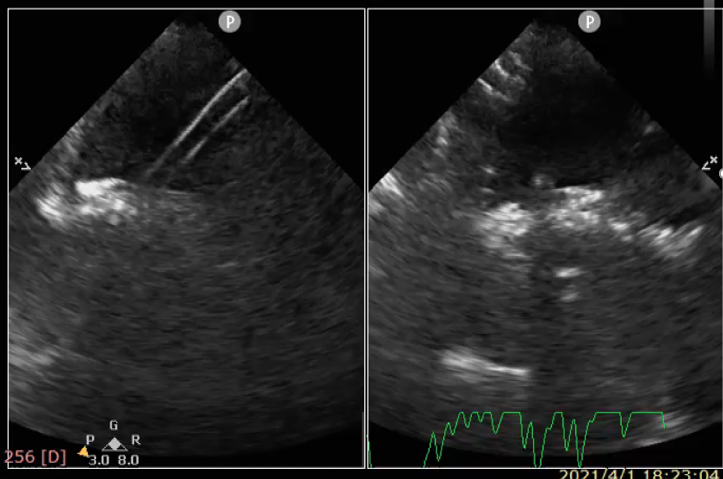

最后,周达新医生介绍ReAces的临床前研究成果。ReAces已设计定型,并完成前期临床前评价,即将进入临床试验。ReAces在专业动物实验机构开展临床前动物实验评价,完成35头猪体内封堵器植入(含对照品)。取材解剖显示45天即已内完全皮化。长期随访期间发现封堵效果良好,未见异常临床现象。通过动物试验发现封堵器再穿操作性良好,植入ReAces 2个月后成功对猪房间隔进行再穿刺,8.5F房间隔穿刺鞘穿过封堵器中央房间隔后,可将14F输送鞘送入左房(图3)

图3 一例植入封堵器2月后动物实现封堵器内再穿刺并送入大鞘管